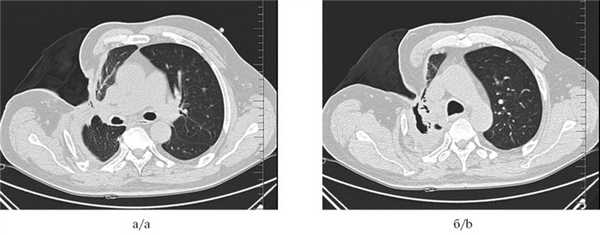

Рис. 4. Мультиспиральные компьютерные томограммы органов грудной клетки до установки клапанного бронхоблокатора (а и б): инфильтративные изменения ткани правого легкого; видны остаточная плевральная полость и торакостома.